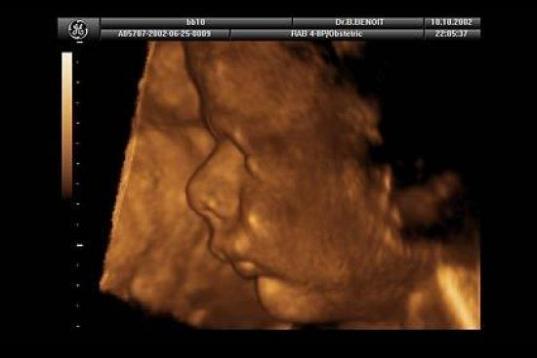

En esta galería puedes ver en fotos como es el desarrollo de un feto de semana en semana:

Desarrollo del feto, en fotos

Ver la galería